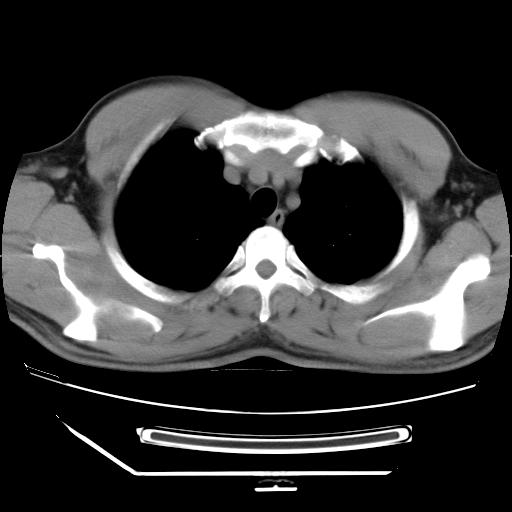

标题: CT21560:胸部肿块影,请会诊

男,38岁,于2009年8月9日晚突发左侧胸痛,今x线提示左下肺阴影,为了明显确诊断,行ct检查,

血常规:嗜酸性细胞增高,单核细胞增高。

纵膈窗

病灶发生在下叶,密度均匀,边缘模糊、毛糙,周围血管纹理增强扭曲改变,靠近胸膜处病灶胸膜反应明显。

支持考虑---球形肺炎。

左肺舌叶病变。主体病灶呈类圆形中心密度低,成液化趋势周边班片影分布

考虑肺脓肿

虽然实验室检查支持炎性病变,且病变内有坏死改变(中央呈大片状低密度影),但仍不能掉以轻心,鳞癌也可以有这种影像改变。